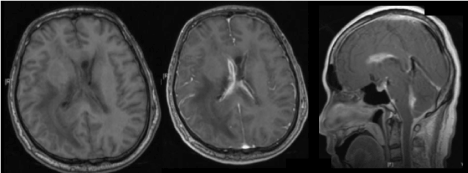

Abnormal enhancement of the ependymal surfaces of the ventricles may reflect concurrent ventriculitis (Figures 9a, 9b and 9c). Other features of ventriculitis include ventricular debris and periventricular FLAIR hyperintensities.

Figure 9. Axial T1-weighted images (a)pre- and (b)post gadolinium administration show abnormal enhancement of the ependymal surfaces in keeping with meningitis with concurrent ventriculitis. (c) Sagittal T1-weighted imaging post gadolinium administration of the same patient demonstrates abnormal ependymal enhancement within the lateral and fourth ventricles.